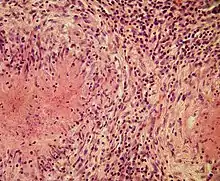

Structurally, epithelioid cells (when examined by light microscopy after stained with hematoxylin and eosin), are elongated, with finely granular, pale eosinophilic (pink) cytoplasm, and central, ovoid nuclei (oval or elongate), which are less dense than that of a lymphocyte.[4] They have indistinct shape and often appear to merge into one another, forming aggregates known as giant cells. When examined by transmission electron microscopy in epithelioid cells in the field of Golgi lamellar complex are taped not only zonated, but also sleek vesicles with dense center, and also great many (more than 100) large granulas with diameters up to 340 nm and with finegranular matrix more light than in macrophage granulas, sometimes with perigranular halo. “The most prominent feature of these cells is the enormous Golgi area; up to 6 individual stacks of Golgi cisternae may be present as well as a few bristle-coated and numerous smooth vesicles”.[5][4] Epithelioid cells have tightly interdigitated cell membranes in zipper-like arrays that link adjacent cells.[3] This cells are central in the formation of granulomas, which are associated with many serious diseases.[4] In granulomas, epithelioid cells perform the functions of delimiting.[3]

Epithelioid cells are an essential characteristic of epithelioid cell granulomas.[10] Epithelioid cell granuloma can be defined as specifically and structurally organized collection of epithelioid cells, macrophages, lymphocytes and dendritic cells. Foreign-body granulomas may be considered an organized collection of macrophages, including mere collections of giant cells surrounding inert substances like suture material – the so-called "non-immune granulomas." Granuloma formation is associated with pathogens that have learned to evade the host immune system by various means like resisting phagocytosis and killing within the macrophages. Indigestibility of matter by macrophages is a common feature of granulomatous inflammation.[4] Granulomas try to wall off these organisms and prevent their further growth and spread. Historically widespread and destructive diseases such as tuberculosis, leprosy and syphilis are granulomatous conditions. Granuloma formation is also the feature of many more contemporary conditions, like fungal infections, sarcoidosis and Crohn's disease.[4]